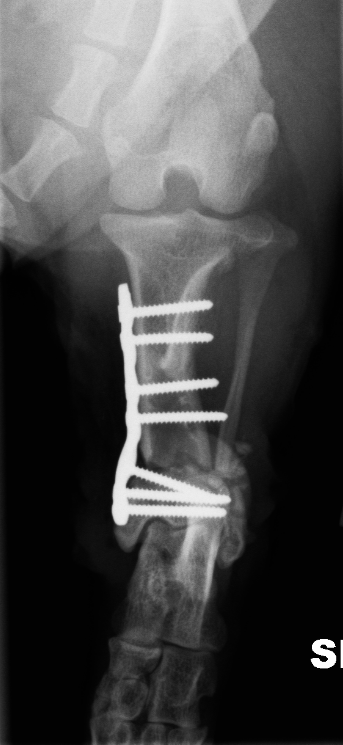

Diagnoosi voidaan varmistaa röntgenkuvauksella ja sairauden hoito on kirurginen. Sääriluun alapää katkaistaan ja luusta poistetaan kolmion muotoinen pala (kuva 2) niin, että jalka saadaan suoraan asentoon. Jalkaan asetetaan metallilevy (kuva 3A), joka poistetaan myöhemmin, kun leikkauskohta on täysin luutunut (kuva 3B). Fysioterapia leikkauksen jälkeen nopeuttaa paranemista. Ajoissa tehdyn leikkauksen ennuste on hyvä, ja suurin osa koirista elää leikkauksen jälkeen normaalin ontumattoman elämän.

Kuva 3: Heti leikkauksen jälkeen otettu röntgenkuva, jossa näkyy, kuinka jalan akseli on nyt suora (A) ja kolme kuukautta myöhemmin ennen levyn poistoa otettu röntgenkuva, jossa nähdään, että sääriluu on täysin luutunut ja jalka on oikeassa asennossa (B).